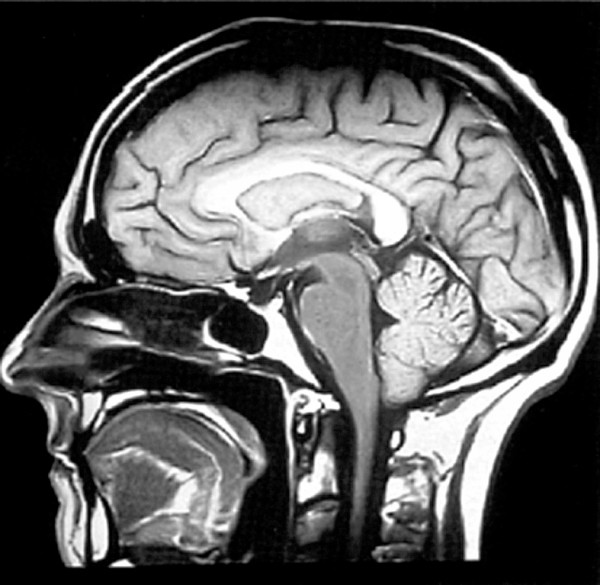

癫痫病是一种大脑神经元细胞异常过度放电而引起的发作性、突然的、暂时性而又反复性的脑功能紊乱。俗称“羊羔风”、“羊角疯”、“猪婆风”。在我国发病率较高,可发生于任何年龄,青少年及妇女尤为多见。临床表现可概分原发性、继发性两种类型。其临床表现呈各种形式,最常见的是意识障碍或意识丧失、突然倒地、四肢抽搐、两眼上视、口吐涎沫、大小便失禁,限局性或全身性肌肉强直性或阵痉性抽搐,行为异常、记忆功能减退、醒后不能回忆发病过程,或植物神经功能紊乱等。据世界卫生组织(WHO)报告显示,癫痫病已成为威胁人类健康的“五大隐形杀手”之一,引起全世界医学界高度重视。

随着二十一世纪医学技术不断发展、创新,一大批高科技医疗设备陆续研发成功并投入临床,为癫痫病的检测提供了科学、可靠的诊断依据。“脑电地形图”和“经颅多普勒”的问世,更堪称人类诊断治疗癫痫病的里程碑,它弥补了癫痫病治疗领域的零设备空白,终结了传统依靠人工问病诊断的历史。数码脑电地形图诊断仪,能在无创、高效、安全的情况下,迅速检测到大脑异常放电频率、强弱及范围等重要依据。经颅多普勒则采用对大脑血流量监测原理,为临床专科医生提供及时快速判断脑部异常放电部位,帮助患者走出诸多误诊、漏诊等盲目误区。“脑电地形图”+“经颅多普勒”双向互动检测,为人类攻克癫痫病作出重大贡献,被医学界誉为诊断“癫痫病”的“黄金搭档”、“扫雷专家”。可以说,中国蛇协副会长成贵芳投资创办的湘潭东方友爱癫痫病专科医院诊疗技术超一流,患者放心做出正确选择。